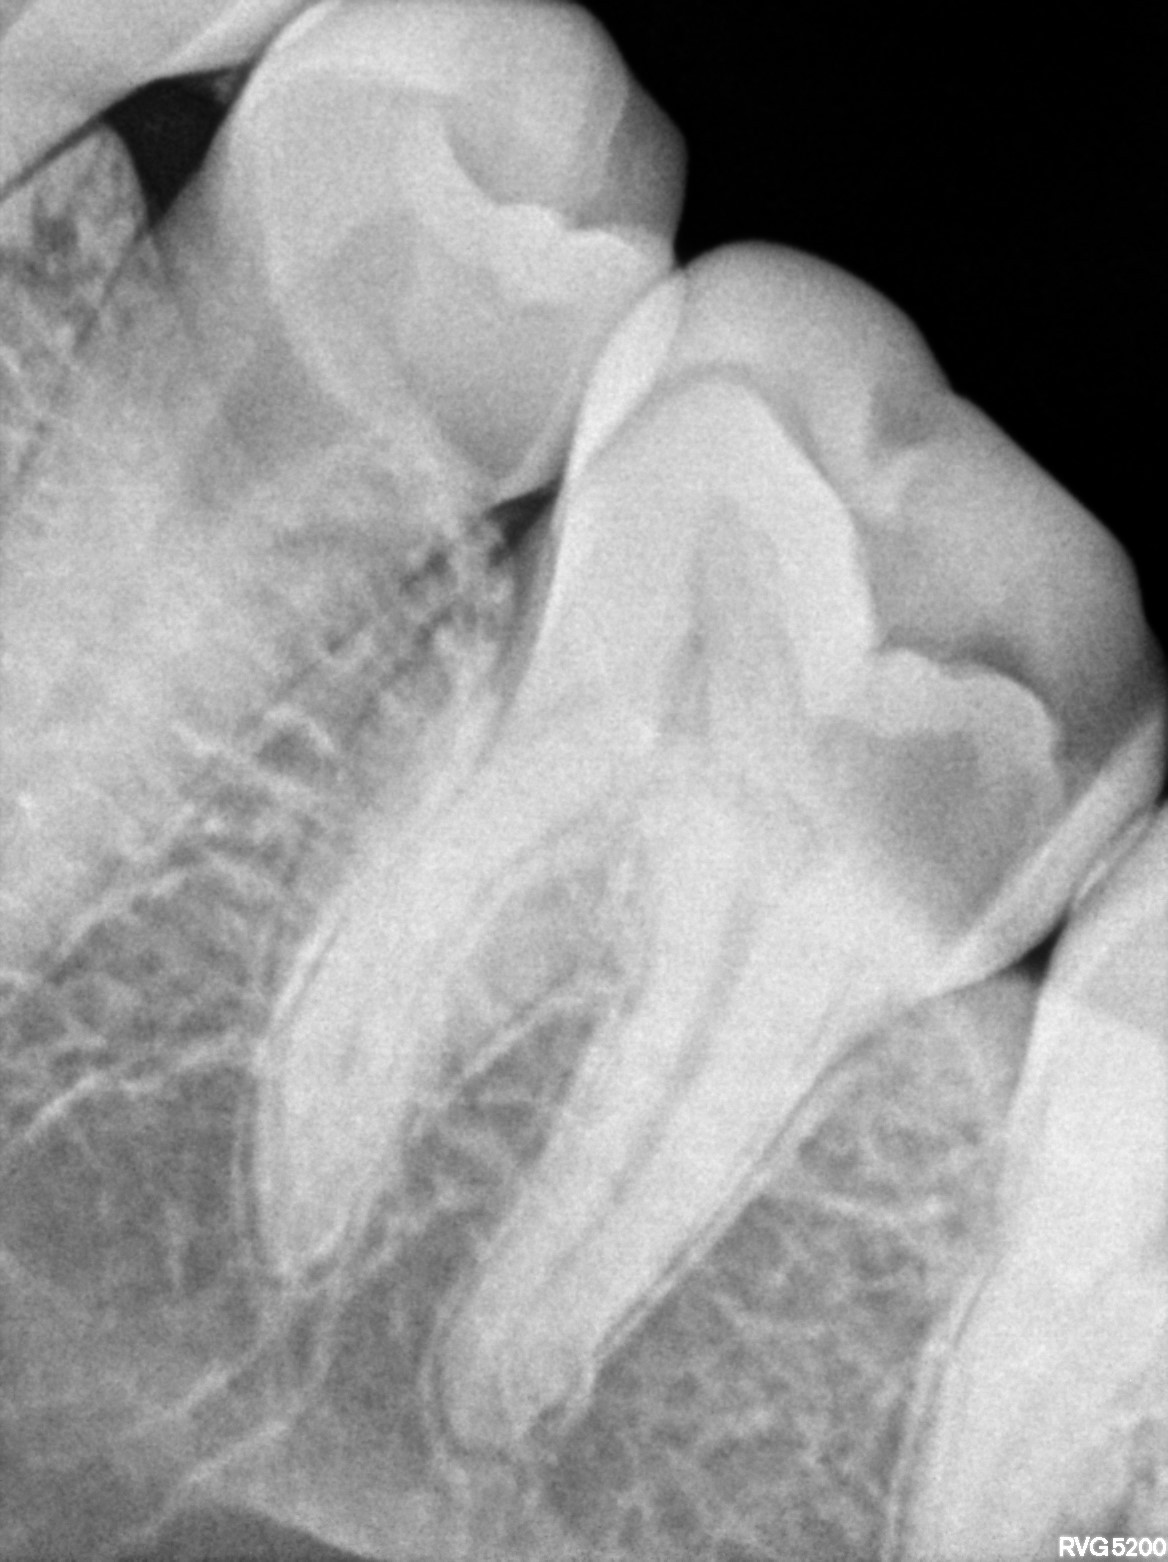

Dental Radiographs FHIR: DocumentReference · LOINC 24641-7

xray_1772180286_0.jpg

24641-7